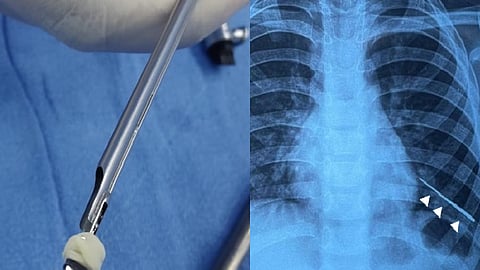

சிறுவனின் உடல்நல குறைவுக்கான காரணம் என்னவென்று கண்டறிய x ray செய்து பார்த்ததில் சிறுவனின் இடது நுரையீரலில் 4 செமீ அளவிலான தையல் ஊசி ஒன்று இருப்பது தெரியவந்தது.

இந்நிலையில் இதற்காக 4.மி,மீ அகலம் மற்றும் 1.5 மி.மீ பருமன் கொண்ட காந்தம் வாங்கிவரப்பட்டு அத்துடன் காந்த நூலை பொருத்தி, ஒரே ஒரு தாடையுடன் ஊடிய சிறப்பு கருவியை கொண்டு இந்த ஊசியை வெளியேற்ற திட்டமிடப்பட்டது. மேலும் நுரையீரலில் ஊசி இருக்கும் இருப்பிடத்தை கண்டறிய எண்டோஸ்கோபிக் செயல்முறை மேற்கொள்ளப்பட்டு சுவாசக் குழாயின் வழியாக இக்காந்தமானது செலுத்தப்பட்டது.

உள்ளே சென்ற காந்தம் உடனடியாக ஊசியை பற்றி பிடிக்கவே சுமூகமாக வெளியில் வெற்றிகரமாக எடுக்கப்பட்டது தையல் ஊசி.